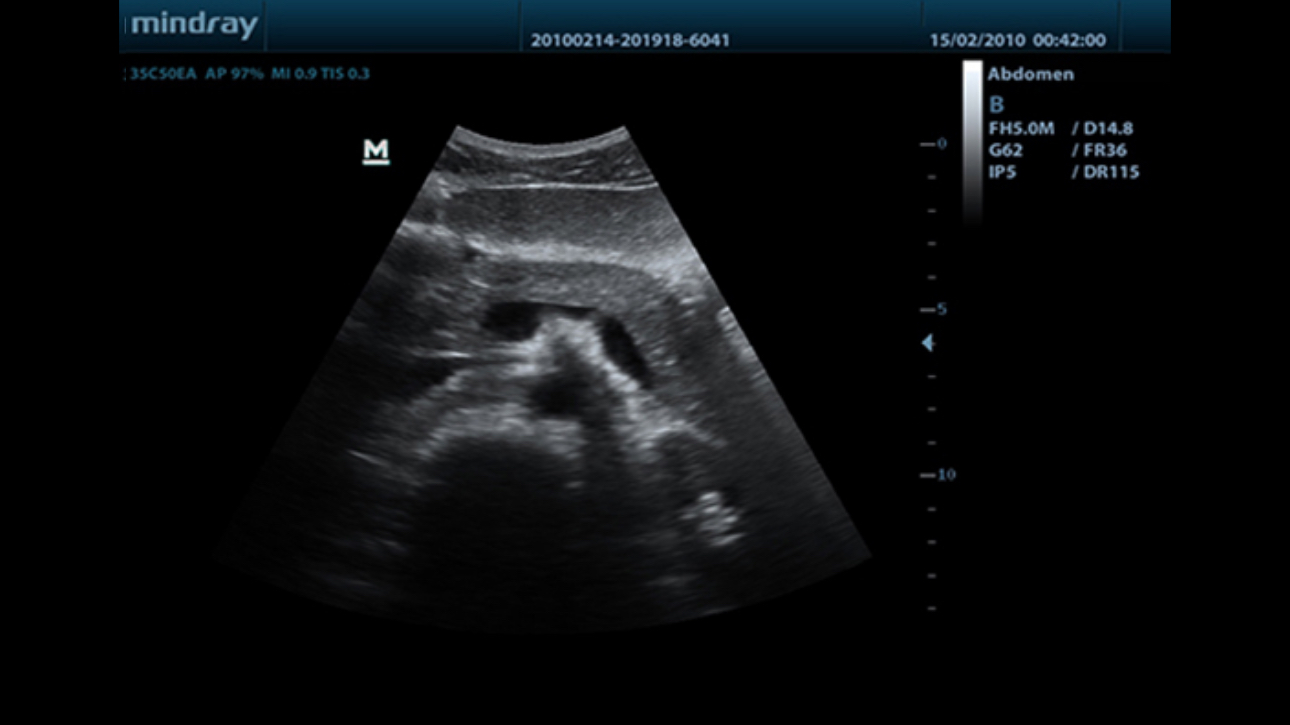

MindrayŌĆÖs new generation of black & white ultrasound system, DP-50, is equipped with advanced imaging technologies allowing deeper penetration and faster image acquisition with higher resolution.? A smart new shape, enhanced mobility and convenient operation make DP-50 well suited for all clinical settings.

ExFOV

Discover better diagnostic information through extended view of the anatomical structure on all convex probes.